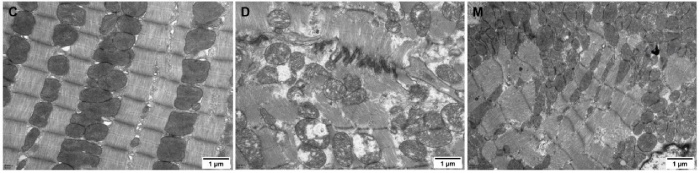

該研究利用透射電鏡測定了MOTS-c對糖尿病心肌超微結構的影響。糖尿病引起心肌纖維排列紊亂和線(xiàn)粒體結構的異常改變,包括心肌細胞排列不規則、嵴破裂、腫脹和空泡化(圖2)。MOTS-c治療糖尿病大鼠顯著(zhù)降低心肌線(xiàn)粒體損傷,改善心肌纖維和線(xiàn)粒體結構(圖2)。研究還通過(guò)測定檸檬酸合酶的活性,測定了線(xiàn)粒體功能。D組大鼠檸檬酸合酶的活性顯著(zhù)降低,C組和M組的檸檬酸合酶的活性無(wú)統計學(xué)差異(圖3g)。

圖2. 各組大鼠心肌組織透射電鏡圖像